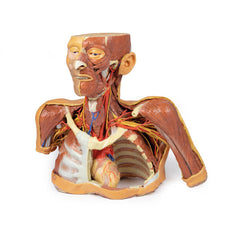

This 3D printed heart has been dissected to display the internal structures of the chambers. At the base of the heart the termination of the superior vena cava is preserved entering the right atrium. Part of the inferior vena cava is also preserved on the inferior aspect of the right atrium; however, most of the vessel lumen and much of the anterior wall has been removed to expose the pectinate muscles of the right auricle and the fossa ovalis (which is nearly translucent in the 3D print).The anterior wall of the right ventricle has also been removed to expose the right atrioventricular valve and its three cusps (anterior, posterior, and septal), including the chordae tendineae connecting them to respective papillary muscles projecting from trabeculae carneae (including a septomarginal trabecula entering the anterior papillary muscle from the interventricular septum). The smooth wall of the conus arteriosus is also exposed leading to the pulmonary semilunar valve (left, right, and anterior cusps) at the base of the pulmonary trunk. Preserved and encircling the right atrioventricular valve is the right coronary artery, ultimately passing to the posterior aspect and the origin of the posterior interventricular artery and atrioventricular nodal artery.

On the posterior side of heart the terminations of the pulmonary veins are visible entering the opened left atrium. Just anterior to the depression of the fossa ovalis in the interatrial septum the left atrioventricular valve with its two cusps (anterior and posterior) is preserved, along with the associated chordae tendineae and papillary muscles in the ventricle.

The walls of the opened left ventricle preserve well-developed trabeculae carneae. At the apex of the ventricle the aortic semilunar valve (with left, right, and posterior cusps preserved) can be seen at the base of the sectioned aorta alongside the origin of both coronary arteries. The left coronary artery in this specimen is very short, giving rise almost immediately from its origin to the left anterior descending artery, the diagonal artery, the ramus intermedius, and the circumflex branch. The latter branch passes between the left atrium and ventricle adjacent to the opened coronary sinus leading to the right atrium. The left anterior descending branch penetrates the myocardium in this individual and travels through the tissue, only emerging superficially to become visible again near the apex.